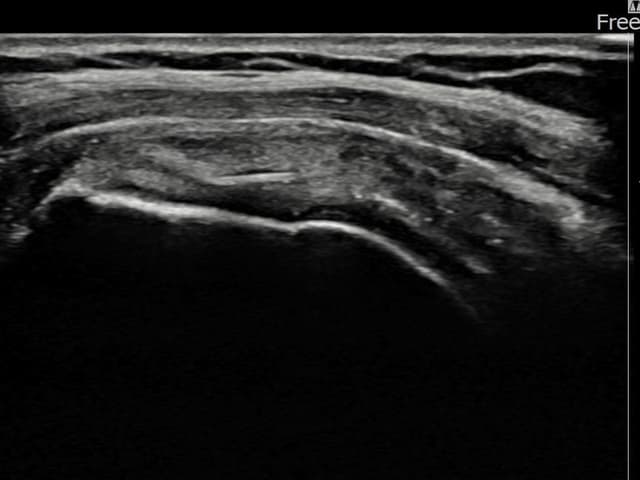

[経過期間: 24.01.08~24.03.14]

[縫縮術] 超音波検査にて左 棘上筋腱 関節面側部分断裂(3.5mm × 3.1mm (부분파열))を確認。縫縮術施行後、腱の連続性が回復し、日常生活に復帰されました。